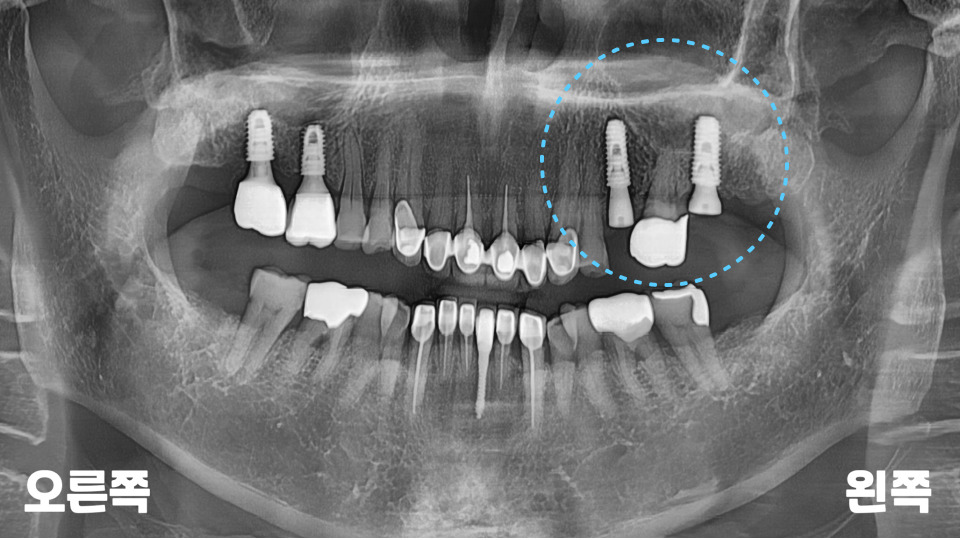

모든 임플란트 마무리 후에

확인을 위한 파노라마를

추가로 촬영해 보았습니다.

위아래로 교합 라인도

턱지지 않고 잘 맞고,

씹을 때도 높지 않고

편안하다고 해주셨는데요.

앞으로 정기적인

6개월~1년 검진을 통해

불편한 점이 있는지

계속 관리해 드릴

예정입니다.